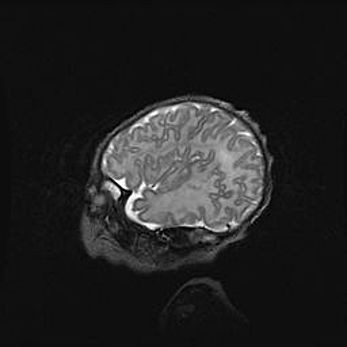

Множественные кисты обоих полушарий головного мозга, наибольшая из них в правой затылочной области. Ассиметричная атрофическая гидроцефалия.

Возраст: 7 месяцев

Вес: 5660 г

Пол: мужской

Окружность головы: 41,5 см

Срок гестации: 28-29 недель

Кисты головного мозга развиваются в результате многоочаговых некрозов вещества мозга и возникают вследствие перенесенной перинатальной инфекции, менингитов, энцефалитов, асфиксии, родовой травмы, расстройств мозгового кровообращения различного генеза. Образованию кист в веществе головного мозга плодов и новорожденных способствуют такие факторы, как высокое содержание в нем воды, недостаточная (или отсутствие) миелинизация и слабая астроглиальная реакция на повреждение.

Кисты могут сочетаться с гидроцефалией и другими поражениями головного мозга.